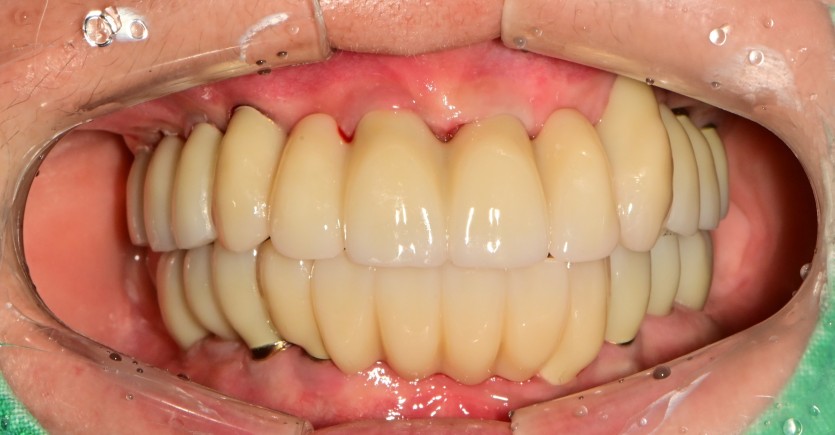

전체 임플란트 증례입니다.

18개의 임플란트로 완성하였습니다.